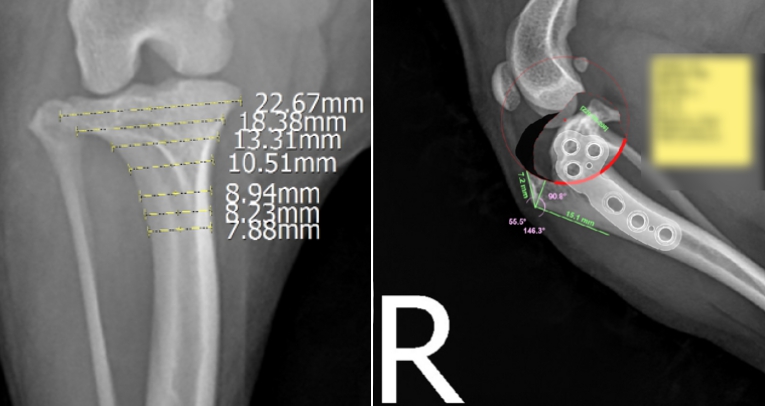

저희 병원은 vpop PRO 프로그램을 사용해서 환자 개개인에 맞는 수술을 계획 할 수 있습니다.

프로그램을 통해 각도를 얼마나 돌릴 지, 어떠한 플레이트와 스크류를 사용하여 고정을 할지 ,수술 후 예상되는 변화는 어떤지 미리 볼 수 있기 때문에 충분한 계획을 가지고 수술을 진행하게 됩니다. ▼